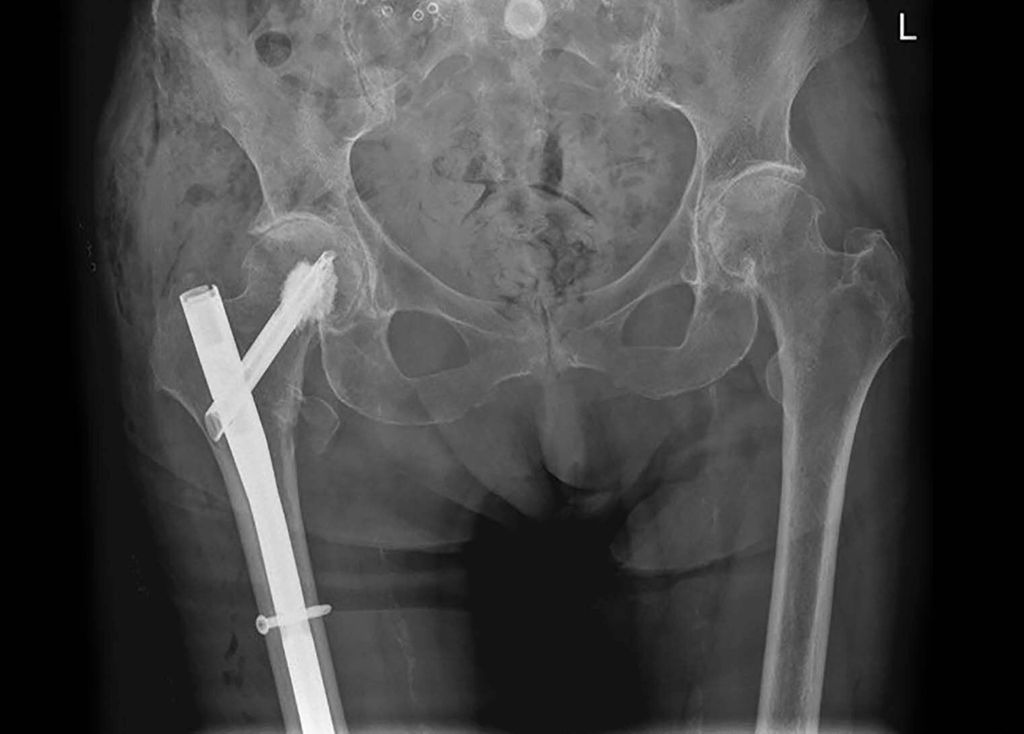

Pertrochantäre Femurfrakturen treten überwiegend bei älteren bzw. geriatrischen Patienten auf und sind daher mit hohen Mortalitäts- und Morbiditätsraten, schlechten funktionellen Ergebnissen und einer eingeschränkten Lebensqualität verbunden. Hierbei sind die Ursachen für eine proximale Femurfraktur bei älteren Menschen vielfältig. Neben einem erhöhten Sturzrisiko, zahlreichen internistischen (z.B. Diabetes mellitus, kardiovaskuläre Erkrankungen) und neurologischen Begleiterkrankungen (z.B. M. Parkinson, Polyneuropathie) sowie weiteren geriatrischen Syndromen wie beispielsweise die Sarkopenie, Mangelernährung oder eine Polypharmazie stellt insbesondere ein fortgeschrittenes Osteoporosestadium, einhergehend mit einer reduzierten Knochenqualität, die größte Herausforderung in der Frakturversorgung dar.2 Eine bewährte Methode zur Stabilisierung dieser Frakturen ist der Einsatz von intramedullären Nägeln, mit oder ohne die Verwendung von Knochenzement (Abb. 1).

Abb. 1: Röntgen Beckenübersicht: Z. n. zementaugmentierter Implantation eines intramedullären Nagels bei Z. n. pertrochantärer Femurfraktur rechts